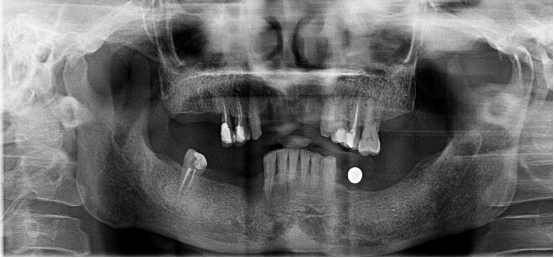

全口種植牙修復(fù)案例

病例簡(jiǎn)介:

郭先生今年67歲,是位白手起家的成功企業(yè)家。早期忙碌的工作讓他疏于口腔保健,導(dǎo)致他上下牙列缺失。郭先生表示在二十年前在國外已經(jīng)做過種植牙,但是近期來我院就診時(shí)其之前種植牙的種植體已經(jīng)滑入到上頜竇內(nèi)。

“患者前牙骨量不足,壁薄,后牙因手術(shù)取出以前的種植體導(dǎo)致了骨頭的大量缺損,所以需要植骨才能進(jìn)行種植牙手術(shù)。種植需要避開手術(shù)后的骨缺失區(qū),所以對(duì)種植體的承受力和穩(wěn)定性要求較高,同時(shí)患者對(duì)美觀要求較高?!眲⒈笤淌谠诹私饬嘶颊叩男枨笈c口腔情況后為他進(jìn)行了植骨手術(shù),傷口愈合后,劉斌元教授為他進(jìn)行CT掃描后確認(rèn)可以進(jìn)行種植牙手術(shù)。

手術(shù)成功結(jié)束,郭先生的全口牙齒全部種上,郭先生表示種牙后感覺很好,使用起來很方便:“終于吃上了我喜歡的堅(jiān)果了!”